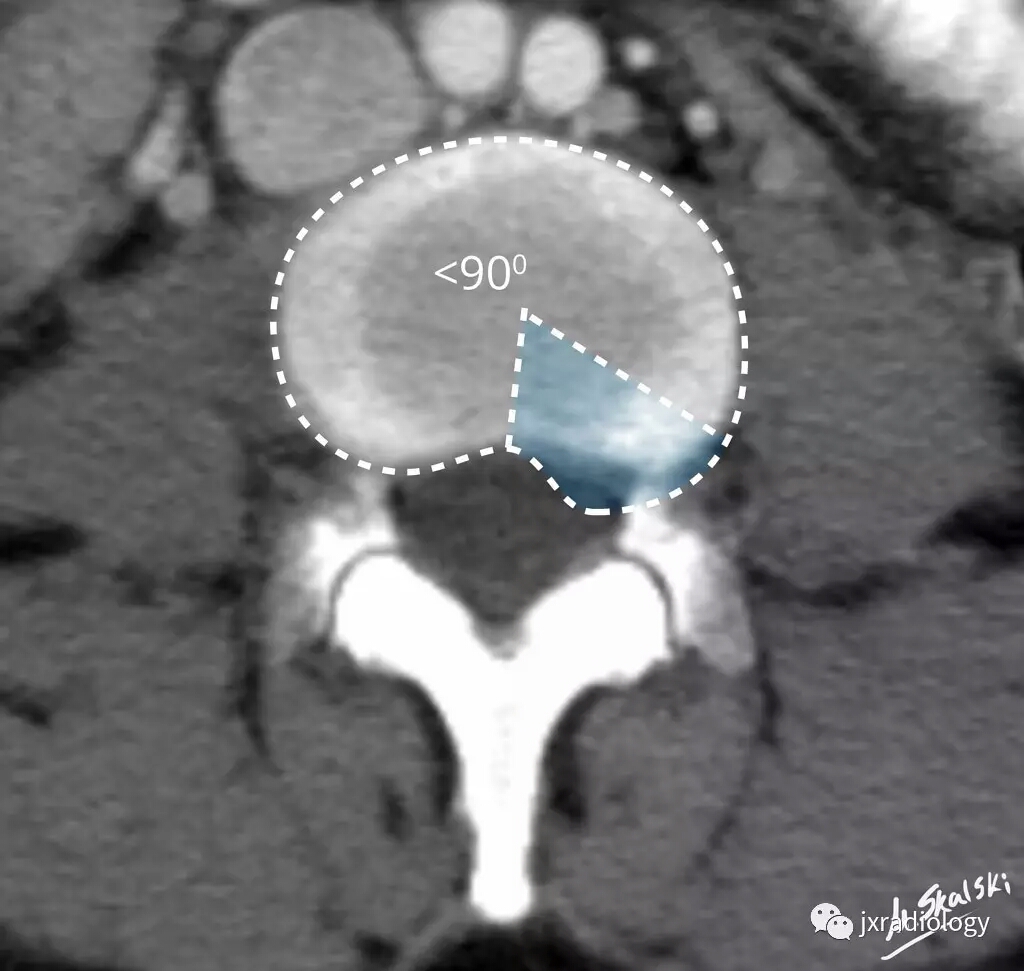

三、椎间盘突出(Disc protrusion)

椎间盘突出物小于椎间盘 25%(90度);而且,任何平面,突出物最大测量值均低于移位椎间盘来源的基底部。